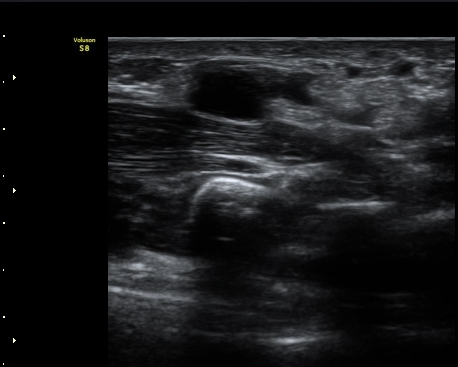

ŽÃËÀÚ¸¦ Á¶±Ý ´õ ¸»´ÜÀ¸·Î À̵¿ÇÏ´Ï Á¤Áß½Å°æ ½ÉºÎ¿¡ Àú¿¡ÄÚ ³¶Á¾ÀÌ °üÂûµÇ°í(»çÁø 4),

³¶Á¾ÀÌ Á¤Áß½Å°æ ¼öÁö °¡Áö¸¦ ¾Ð¹ÚÇÏ´Â ¸ð½ÀÀÌ °üÂûµÈ´Ù(»çÁø 5, 6, 7).